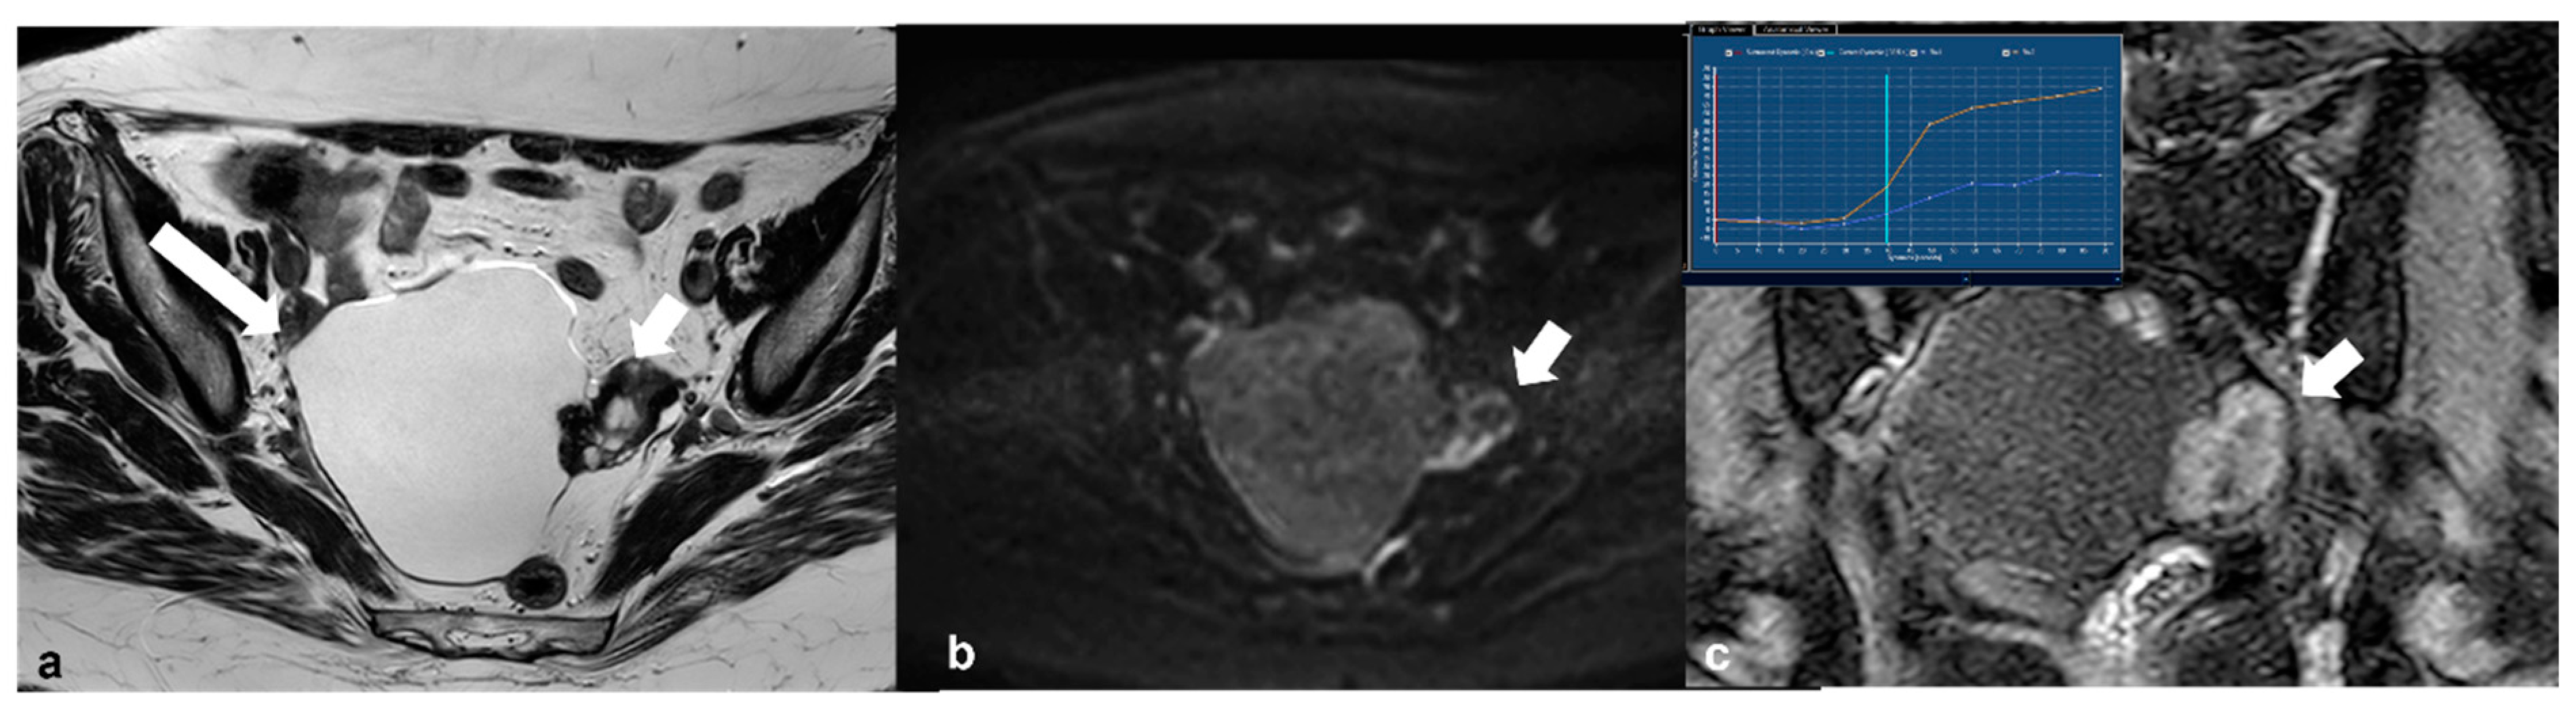

2.3.4. Lymphoma

2.3.5. Metastases